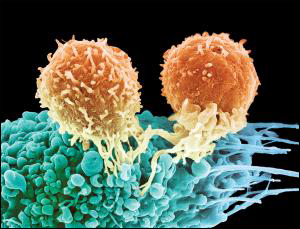

Ученые и врачи с помощью новой технологии вылечили от рака смертельно больного человека. Новая методика может стать мощным лекарством для лечения онкологических и многих других заболеваний.

Онкологические заболевания, к сожалению, очень распространены и к тому же стоят на пути к радикальному продлению жизни. Современные средства лечения рака не очень надежны, но ученые, возможно, нашли эффективное средство лечения всех видов рака, а также множества других заболеваний. Суть новой технологии заключается в «обучении» иммунных клеток пациента борьбе с клетками рака. Первые успешные опыты по лечению пациентов в тяжелом состоянии продемонстрировали высочайшую эффективность новой методики.

Нику Уилкинсу был поставлен диагноз лейкемия, когда ему было всего 4 года. К сожалению, ни химиотерапия, ни пересадка костного мозга от его сестры не помогли избавиться от болезни. К 14 годам стало ясно, что все существующие способы лечения не помогают, а значит Ник скорее всего умрет. К счастью, мальчика включили в экспериментальную программу лечения, разработанную в Университете Пенсильвании. Вместе с 20-ю другими молодыми пациентами Ник Уилкинс прошел курс экспериментального лечения в Детской больнице Филадельфии. На этих выходных на ежегодном собрании Американского гематологического общества врачи представили доклад об успешном завершении эксперимента. Удивительно, но уже через 2 месяца после лечения Ник полностью избавился от рака. Из 21 пациента у 18 наблюдалось полное излечение всего лишь после одного курса лечения.

Новая терапия основана на использовании Т-клеток иммунной системы пациента и, при должной квалификации врачей, потенциально может быть осуществлена в любом современном медицинском центре. Лечение проходит следующим образом: сначала врачи берут у пациента иммунные Т-клетки и перепрограммируют их путем передачи в новых генов. Модифицированные клетки «нацеливают» на определенные раковые клетки, и таким образом Т-клетки пациента приобретают свойство обнаруживать и атаковать опухолевые клетки. После перепрограммирования, Т-клетки вводят в тело пациента, у которого ранее эти самые клетки были взяты. В теле человека каждая перепрограммированная клетка передает свою новую генетическую модификацию 10 000 других клеток. Таким образом, в организме пациента появляется большое количество «охотников», которые начинают уничтожать раковые клетки. По сути, ученые «обучили» иммунитет бороться с раком точно так же, как он борется, например, с простудой.

У лечения есть свои особенности, так, после введения модифицированных клеток началась активная борьба с раком, которая вылилась в обычные симптомы борьбы с инфекцией: высокая температура, слабость и т.п. В это время пациентов держали в отделении интенсивной терапии, например Ник Уилкинс провел там день. Однако побочные эффекты нового лечения не идут ни в какое сравнение с тяжелейшим отравлением организма в результате противораковой химиотерапии или опасностями и болезненностью операции по пересадке костного мозга.

Новая технология лечения позволяет «научить» иммунные Т-клетки атаковать клетки опухоли. Подобная методика, теоретически, может применяться для лечения любых видов рака на любой стадии, а также многих инфекционных заболеваний и тяжелых отравлений

Новая методика очень эффективна. У Ника спустя 2 месяца после лечения в крови не обнаружено ни одной раковой клетки. Более того, генетически модифицированные Т-клетки выжили и могут существовать в крови пациентов в течение минимум 3 лет. Это значит, что пациенты надежно защищены от рецидива болезни собственной иммунной системой.

Врачи смотрят на новую технологию оптимистично. Клинические эксперименты с ней ведутся лишь с 2010 года, но до сих пор количество рецидивов остается очень низким, в том числе и у взрослых пациентов. Так, из 12 полностью излеченных взрослых, только у одного наблюдался рецидив, причем рецидивы после терапии модифицированными Т-клетками поддаются лечению намного легче.

Сегодня новая методика лечения доступна лишь в ходе экспериментальных клинических программ, но врачи полагают, что через 3-5 лет она станет обычной клинической практикой.

«Пятнадцать лет назад я был в лаборатории и смотрел, как модифицированные Т-клетки убивают раковые в чашке Петри. Затем были эксперименты на мышах и, наконец, лечение людей, – рассказывает доктор Ренье Брентьен (Renier Brentjens). - Я никогда не забуду первого пациента, у которого в костном мозге было огромное количество раковых клеток. Но после новой терапии, я посмотрел в микроскоп и не смог найти ни одной раковой клетки. Это просто фантастика».